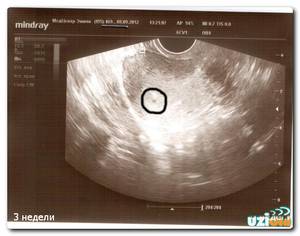

Ультразвуковая диагностика

Третья акушерская неделя не является обязательным сроком для проведения ультразвукового исследования, однако это время предоставляет возможность для тщательной оценки состояния плода и уточнения срока беременности. На первом триместре врач, проведя необходимые измерения и сопоставив их с соответствующими таблицами, сможет довольно точно определить срок беременности, основываясь на размерах эмбриона. В последующие месяцы внутриутробного развития плоды могут значительно различаться:

Поэтому в первые недели беременности ультразвуковое исследование позволяет с высокой точностью установить срок беременности.

Кроме того, ультразвуковая диагностика помогает выявить внематочную беременность и такие состояния, как замершая (неразвивающаяся) беременность. В современной медицине существуют бережные методы, которые, при своевременном обращении к специалисту, могут помочь сохранить репродуктивные функции женщины, что в будущем даст ей возможность стать матерью.